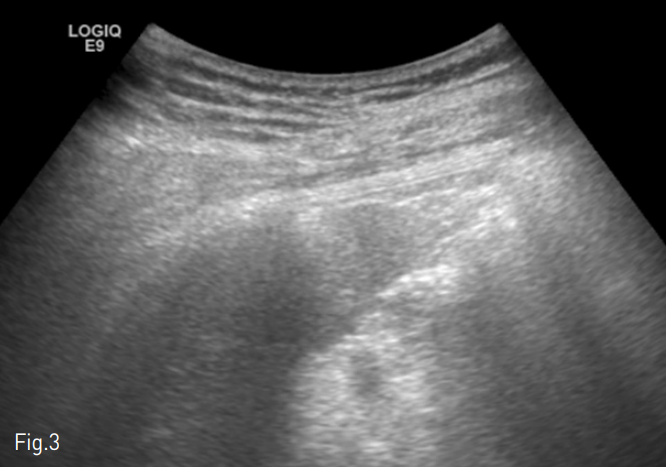

Fig. 3

Gray scale ultrasound image shows linear hyperechoic Jackson-Pratt drainage catheter at the subcutaneous peritoneal area.